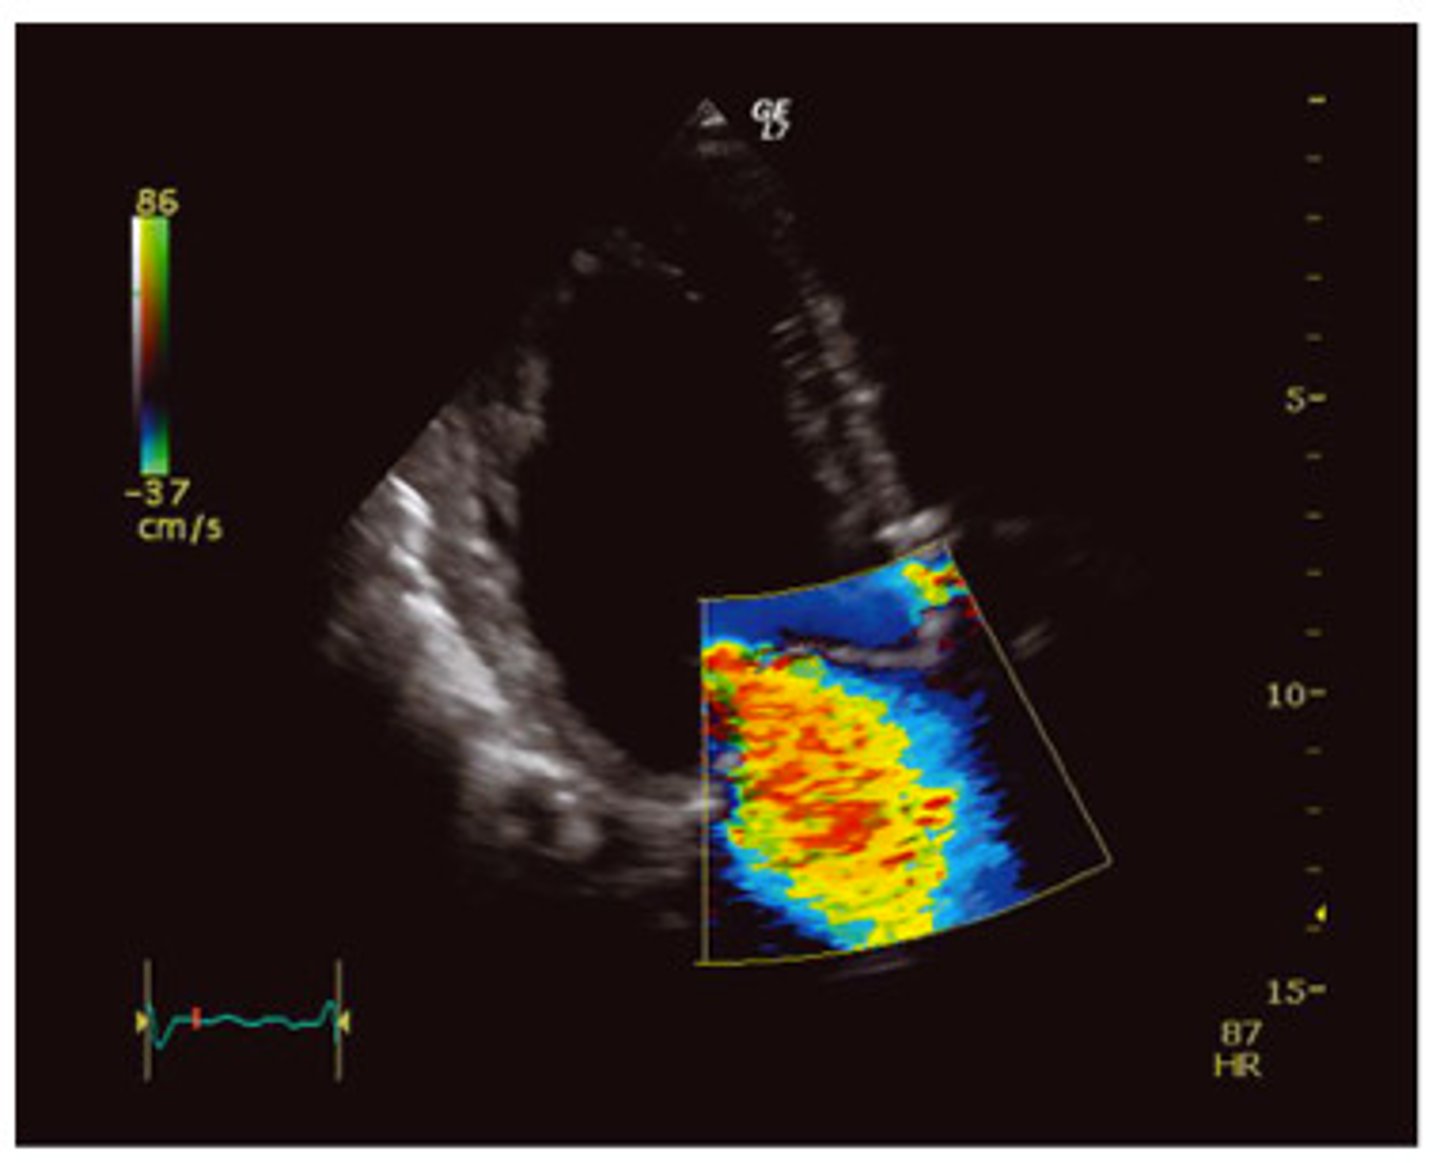

Referencing the image at the right, what type of flow pattern is demonstrated?

pulsatile

phasic

steady

To which part of the respiratory cycle is the yellow arrow pointing in the spectral Doppler image of the lower extremity vein?

inspiration

expiration

From the appearance of the vessel in this image, is this an artery or a vein?

artery

vein

The yellow arrow is pointing to which of the following:

septation

tumor

valve

muscle